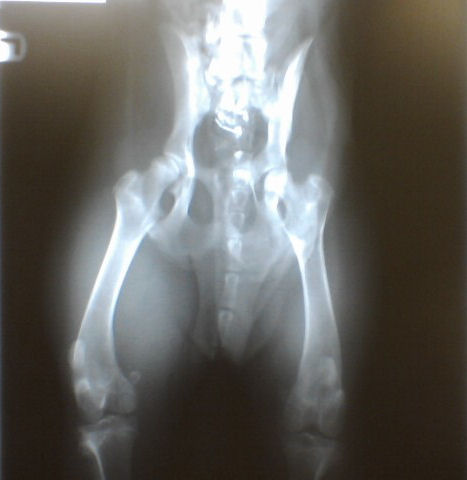

After 6 weeks of rest (loosely defined more recently as keeping her to a dull roar) to heal injuries sustained when a truck ran over her, Jade had her first non-emergency vet appointment on Friday. She got vaccinated and had some blood work done (all normal and heartworm negative). But the main attraction was determining how well her fractured pelvis had healed. I brought my vet an image of the x-ray taken at the emergency clinic on the day of the accident and she found 3 fractures on it (I had only been advised of 2 at the time). She did a physical exam and took a new x-ray. This is a photo of that x-ray:

My vet explained that, while her fractures had healed, she had (and I’m paraphrasing here) healed crooked. Specifically, the ball of the right hip was no longer sitting as it should in the socket. I remember the emergency vet had warned me about the possibility that she may not heal as good as new so although I was prepared, I admit I had been hoping to hear that everything was perfect. My vet said it’s possible she might go through life just fine, simply managing the right hip condition as-is or she may require a femoral head ostectomy at some point. I will monitor her for any signs of pain, particularly on that right side. But the very good news was that the vet gave the all-clear to let Jade rough house, run wild and generally act like a normal 9 month old pitbull puppy.